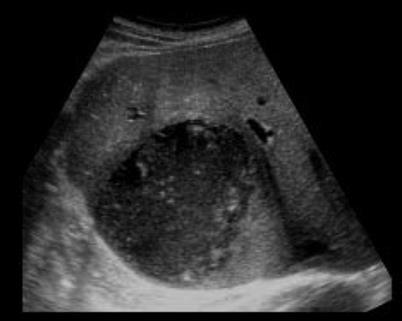

Amebiasis and Amebic Liver Abscess in Children

ABSTRACT

Although rare in the developed world, amebiasis continues to be a leading cause of diarrhea and illness in developing nations with crowding, poor sanitation, and lack of clean water supply. Recent immigrants or travelers returning from endemic regions after a prolonged stay are at high risk of developing amebiasis. A high index of suspicion for amebiasis should be maintained for other high-risk groups like men having sex with men, people with AIDS/HIV, immunocompromised hosts, residents of mental health facility or group homes. Clinical presentation of intestinal amebiasis varies from diarrhea to colitis and dysentery. Amebic liver abscess (ALA) is the most common form of extraintestinal amebiasis. Various diagnostic tools are available and when amebiasis is suspected, a combination of stool tests and serology should be sent to maximize the yield of testing. Treatment with an amebicidal drug such as metronidazole/tinidazole and a luminal cysticidal agent such as paromomycin for clinical disease is indicated. However, for asymptomatic disease treatment with a luminal cysticidal agent to decrease chances of invasive disease and transmission is recommended.

Amebic liver abscess on ultrasound